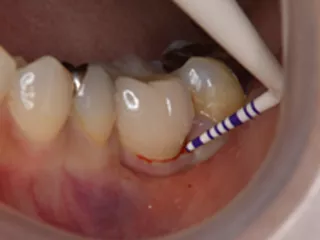

CASE No.4 大月 基弘 先生(大阪府大阪市開業)

Labrida 施 術 前

施 術 前 (レントゲン写真)

Labrida 施 術 後(2週後 )

PPD7㎜からPPD3㎜、

BOP(ー)に変化、炎症消失